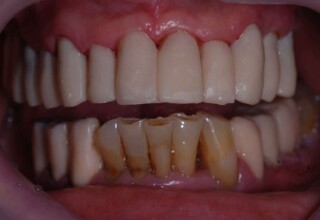

Full mouth prosthetic reconstruction on implants with a different approach on upper and lower jaw

Lower jaw: extractions, direct implant placement and immediate loading (same day) with a transitional bridge.

Upper jaw: Sequential extractions, sequential implant placement and gradual incorporation in the temporary bridge so that the patient was never left without fixed teeth. The aim of the above approach was to have the patient in continuous functional and aesthetic reconstruction, without immediate loading due to anatomical restrictions. Old smiling photos of the patient were used because the natural shape of the teeth was completely lost due to repetitive prosthetic attempts. Tooth relationship and teeth-lip support was transferred to the temporary restorations. Two different transitional bridges were needed to fully estimate phonetics, mastication and esthetics. After the necessary adjustments were finalized, the temporary bridge was used as a guide for the permanent bridges.

Initial smile

Final Smile